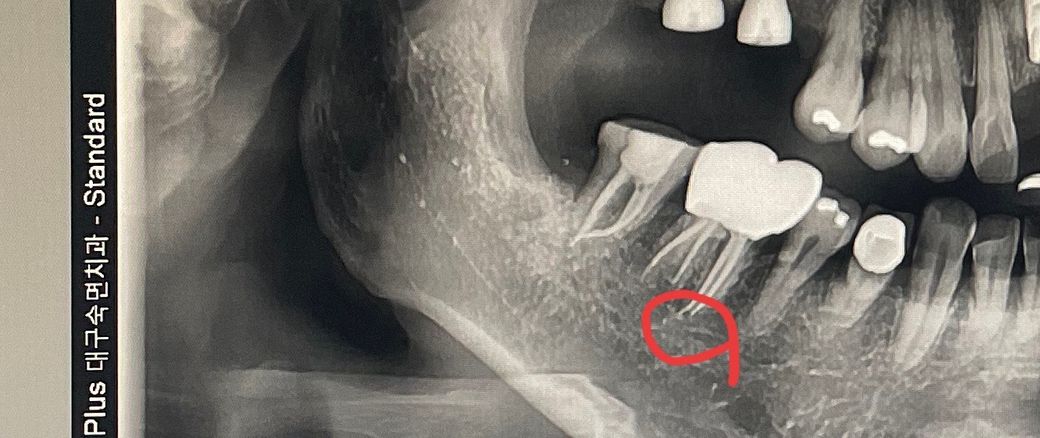

신경치료한 치아가 열감이 있어요 잘못됐나요

신경치료한 치아가 욱씩 열감이 두달째있는데

충전재가 오바된 경우가 아닌가

치료한 치과에서는 이상없다고하고

다른치과에서는 충전재오바라고합니다

씹은땐 통증이없지만 열감이 계속있어요

거타퍼챠 충전재가 약간 오버되긴 했는데 그게 치료결과에 영향을 미칠 정도는 아닐 것 같습니다 그 뒤 치아도 신경치료를 최근에 마친 것 같아서 일단 원인치아부터 정확히 확인이 필요합니다